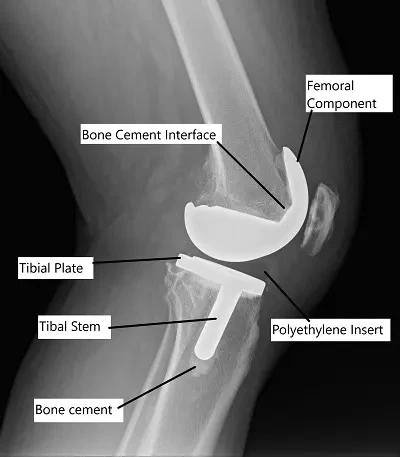

In knee replacement, the worn-out cartilage and bone are removed, and prosthetic implants are inserted. The implant fixation method, whether cemented or cementless, affects the long-term performance of the knee joint.

- Cemented Total Knee Replacement: Prosthetic components are fixed to the bone using bone cement. This method is most commonly used and offers immediate stability.

After thoroughly washing the cut segments, acrylic bone cement is applied to the implants and the bone segments. The implants are then fixed to the prepared bed on the bone.

A plastic high-quality polyethylene space is attached to the tibial component to reduce friction between the implants. The acrylic cement hardens quickly providing immediate fixation.